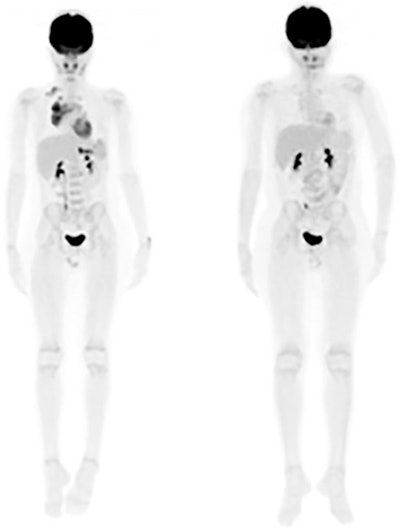

FDG-PET images are from a 12-year-old male diagnosed with clinical stage II non-Hodgkin's lymphoma. Staging PET image (left) shows no lymphoma lesions outside the regular field-of-view. Interim PET image (right) shows a complete metabolic response after two cycles of chemotherapy. Patient was disease-free at 12-month follow-up. Images courtesy of JNM."Our evidence reinforces that regular field-of-view PET/CT is sufficient in pediatric lymphoma, both at staging and interim assessments," the researchers concluded, adding that the findings do not suggest a routine field-of-view approach is applicable to other pediatric tumors.